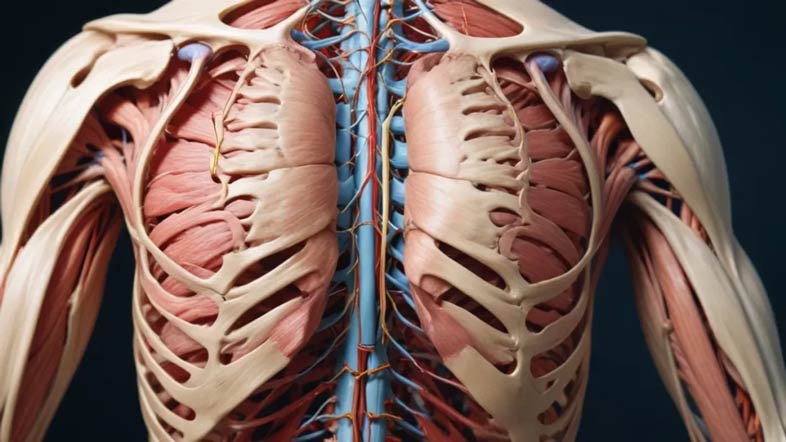

مشکلات عضلانی و اسکلتی

یکی از شایع ترین علل درد شانه چپ فشار یا آسیب به عضلات و بافت های نرم است :

- التهاب تاندون ها : به ویژه در ورزشکاران یا افرادی که فعالیت های تکراری انجام می دهند.

- کشیدگی عضلانی : ناشی از فعالیت سنگین یا وضعیت نشستن نامناسب.

- آرتروز شانه : در اثر تخریب غضروف مفصل شانه ایجاد می شود.

فشار عصبی

- گیر افتادن عصب گردنی (Pinched Nerve) : درد عصبی شانه چپ ناشی از فتق دیسک گردن یا فشار بر ریشه های عصبی.

- نورالژی براکیال : التهاب یا آسیب عصب براکیال می تواند درد تیرکشنده در شانه ایجاد کند.

مشکلات ریوی

- پلوریت (التهاب پرده های ریه) : که می تواند درد ارجاعی به شانه ایجاد کند.

- پنوموتوراکس (فروریختگی ریه) : با درد شدید و ناگهانی شانه همراه است.